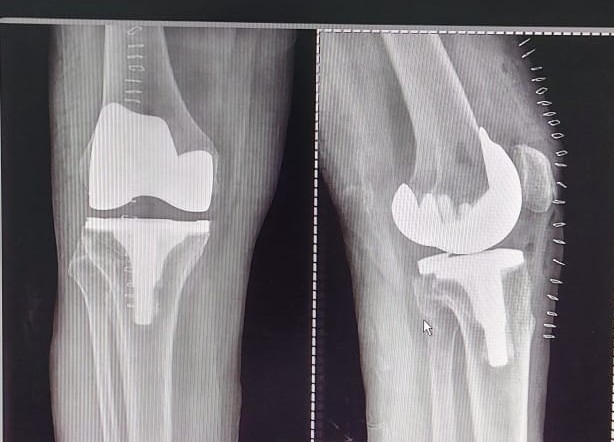

Knee and Hip Replacement